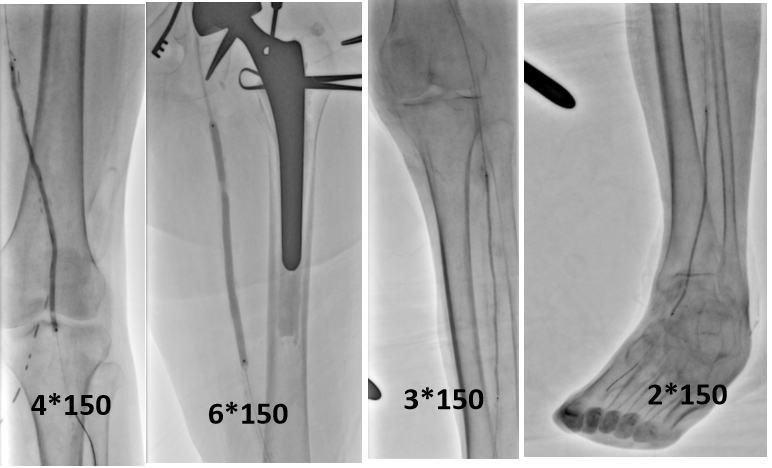

图为:左股动脉内膜剥脱

图为:术前造影:腘动脉P3胫前起始部显影

图为:导丝进入ATA,远端无法回真腔

图为:足背动脉穿刺对接

图为:药涂球囊扩张图为:药涂球囊扩张

图为:支架植入

图为:术后造影